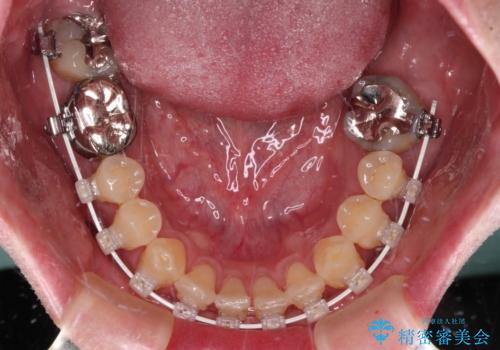

受け口を治す ワイヤー装置での矯正治療

- 上下前歯の反対咬合と左下奥歯の痛みを気にして来院された患者様です。

また、左下の奥歯は親知らずの影響で手前の歯の歯根までむし歯になってしまったため、親知らずとともに抜歯をし、インプラントによる補綴治療を行うこととしました。

矯正治療は、ワイヤー装置とマウスピース矯正との選択肢がありましたが、マウスピース矯正は自己管理が煩わしいことを気にされて、目立たないワイヤー装置にて行うこととしました。

インプラント埋入による仮歯の装着や、前歯の反対咬合の改善は比較的スムーズに達成されましたが、舌突出癖などの影響による、歯列全体のスペースを閉じることが難航し、期間がかかってしまいました。